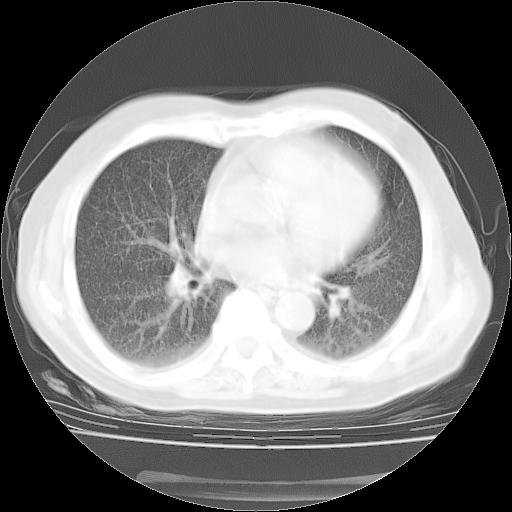

肺部CT平扫未见异常。